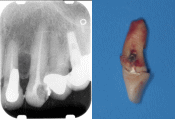

| 前歯の作り直しを希望して来院されました。色・形態・大きさなど審美的ではありません。 |

精密検査の結果、骨の中で歯が割れていることが判明しました。残念ながら抜歯となりました。 |

通常抜歯した部分の歯茎はすぐに痩せてしまいます(○の部分)。外科的に歯茎を増やさなければ美しい歯を入れることはできません。 |